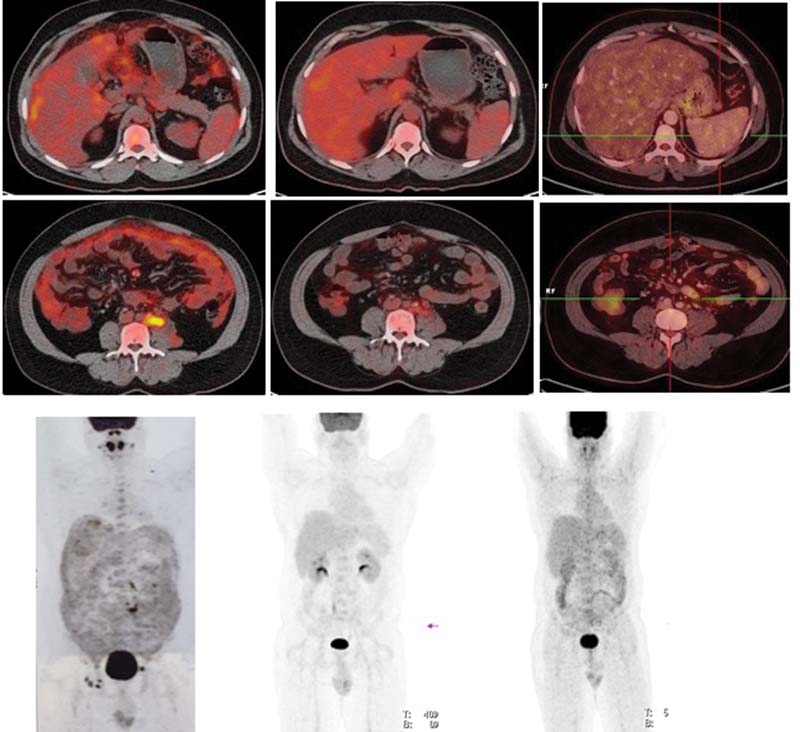

FDG PET/CT scan in March 2019 showed diffuse omental FDG uptake (SUVmax 4.2) with no evidence of nodal involvement (stage IIE) ([Fig. 1]). Laparoscopic omental biopsy was done in April 2019.

|?Fig. 1Fluorodeoxyglucose positron emission tomography fused images in March 2019 (left)?at the time of relapse, October 2019 (center)?after salvage chemotherapy and December 2020?13 months after transplant. Maximum intensity projection images in March 2019 (left)?at the time of relapse, October 2019 (center)?after salvage chemotherapy and December 2020?13 months after transplant.

FDG PET/CT scan 6 weeks after three cycles showed complete metabolic response ([Fig. 1]). There was a detailed discussion with patient and his immediate family members about long-term outcome, high risk of disease relapse, limited available treatment options, and the risks and benefits associated with HDCT/ASCR. He was also explained risk of transplant-related mortality and exacerbation of preexisting HIV infection and tuberculosis.

Patient has been on monthly follow-up with clinical examination and imaging. He is asymptomatic and has gained weight. His hemogram, liver, renal function tests, serum LDH in December 2020 are normal. PET CT scan in December 2020 ([Fig. 1]) showed no evidence of disease, translating into disease-free survival (DFS) of 13 months after the transplant.